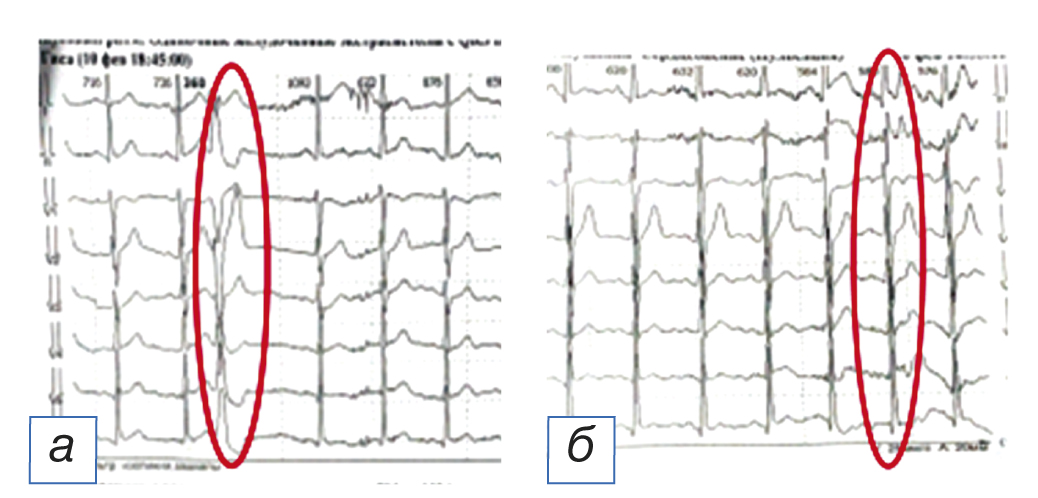

Пациенту проведены эхокардиография, холтеровское мониторирование электрокардиограммы (ЭКГ). По результатам инструментального обследования отмечались частая желудочковая эктопическая активность (одиночные экстрасистолы) (рис. 1) и парные полиморфные экстрасистолы, соответствующие IVb градации по Лауну–Вольфу–Райяну (рис. 2), а также единичная наджелудочковая эктопическая активность и 10 пауз за счёт синоатриальной блокады (рис. 3). В качестве антиаритмической терапии был назначен пропафенон по 150 мг 2 раза/сут.

Рис. 2. Парная желудочковая экстрасистола (а, б).

Рис. 6. Одиночная желудочковая экстрасистола (а, б).